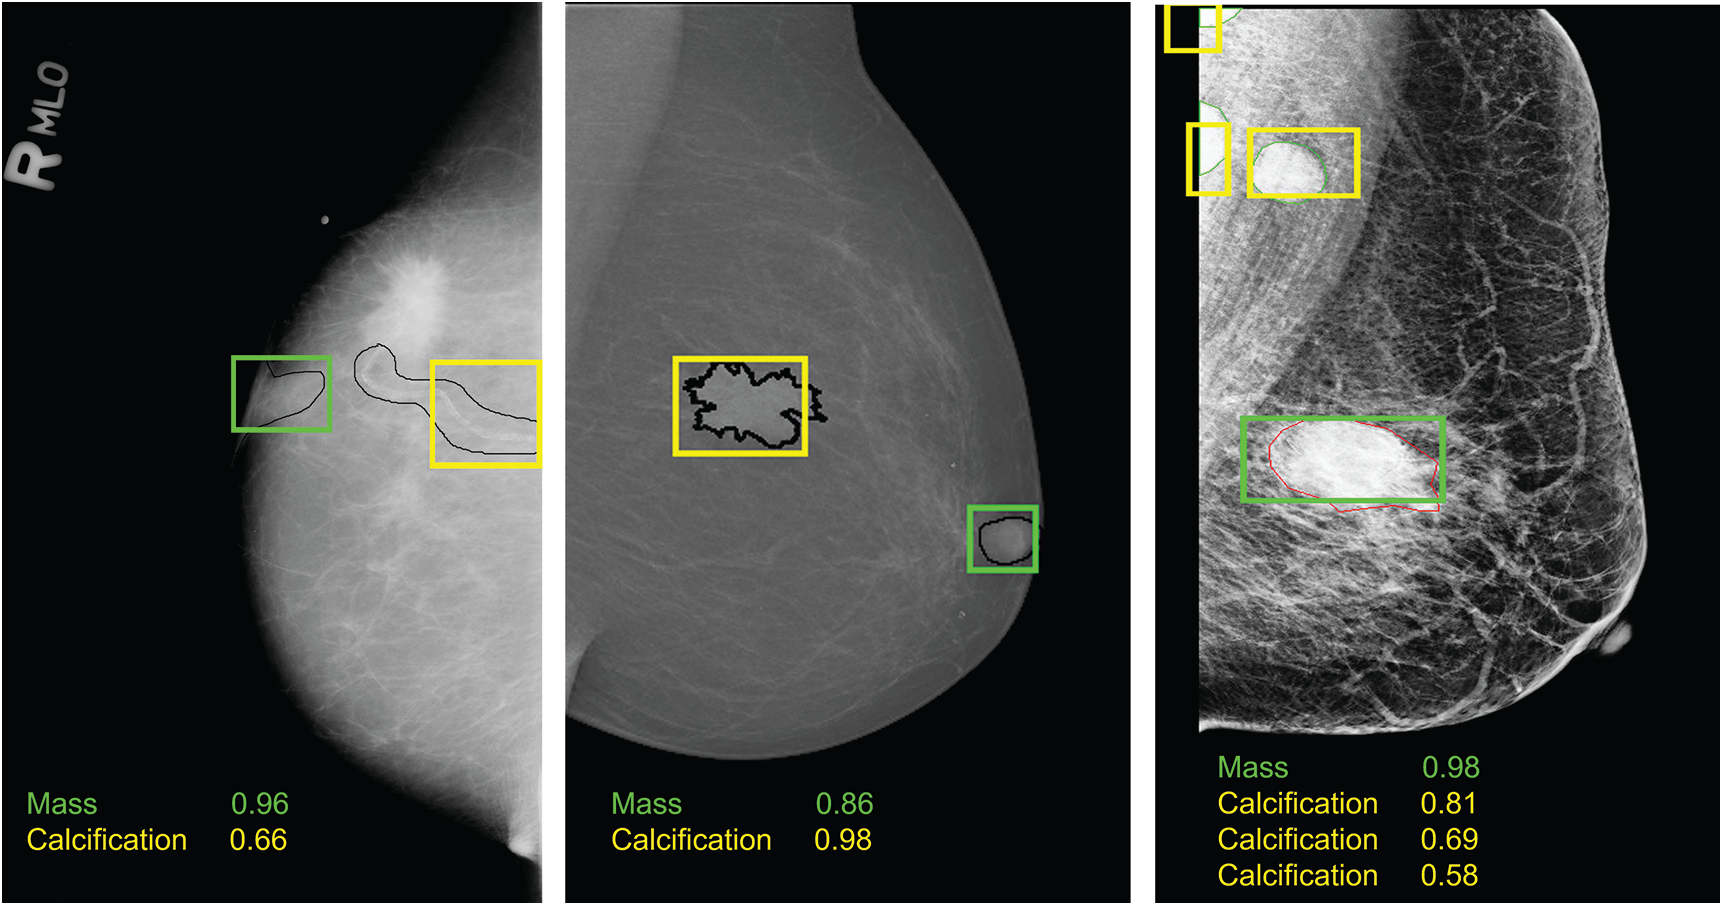

Moreover, Tab. 2 demonstrates that training the model on both prediction classes slightly decreased the performance and this can be explained by the inability of YOLO-based model to detect and distinguish some different types of lesions having similar shapes. However, we proved the robustness of our suggested model toward mass detection with a maximum detection accuracy rate of 96.2 using the private dataset. All experiments had similar inference time with a maximum value of 0.58 seconds. Examples from each dataset are illustrated in Fig. 6, and each lesions breast has its confidence score. We clearly notice that multiple lesions were accurately detected in the same mammogram.

Figure 6: Examples of breast lesions detection and classification results and their confidence score toward different classes on CBIS-DDSM, INbreast and private datasets (from left to right): mass (green boxes) and calcification (yellow boxes)

Furthermore, this approach revealed the advantage of YOLO model as detector and classifier toward different clinical mammographic images (i.e., digitized X-rays, full-field digital mammography, etc.). The quality of predicted images also affirms the robustness of YOLO to successfully identify breast lesions over pectoral muscle, next to breast nipples, or above the dense tissues as shown in Fig. 6. Experimental results showed that training YOLO-based deep learning model is overall fast and accurate, where our results outperform the SSD method [35], the Faster R-CNN model [44], the CNN model [17] and other machine learning techniques [8,16] that had a maximum detection accuracy rate of 98% on INbreast dataset but a significantly high inference time. The comparison revealed that YOLO model is the right choice for mass detection in mammography as presented in other existing YOLO implementations [41,43,44] with a maximum detection accuracy rate of 97.27% on INbreast dataset, and our study enhanced the state-of-the-art results to be 98.1%. However, limitations of the proposed YOLO model can occur in the training configuration that depends on preparing the right format of input data. Thus, input images should be accompanied by the true locations and class labels of the lesions during the training. This requires extracting the coordinates of lesions from the ground truth and consequently YOLO model has an input dependency.